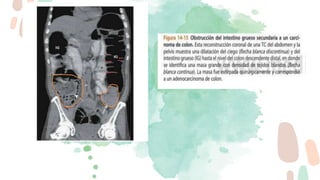

Los puntos más importantes son detectar el punto de transición, determinar la causa y

descartar la presencia de complicaciones.

Para facilitar la búsqueda del PT se emplean dos signos:

El “signo del pico”, dado que el punto de cambio de calibre simula un pico.

El “signo de las heces”, dado que debido a la obstrucción en el PT las heces se acumulan

proximalmente a este dando la típica imagen de patrón en miga de pan.